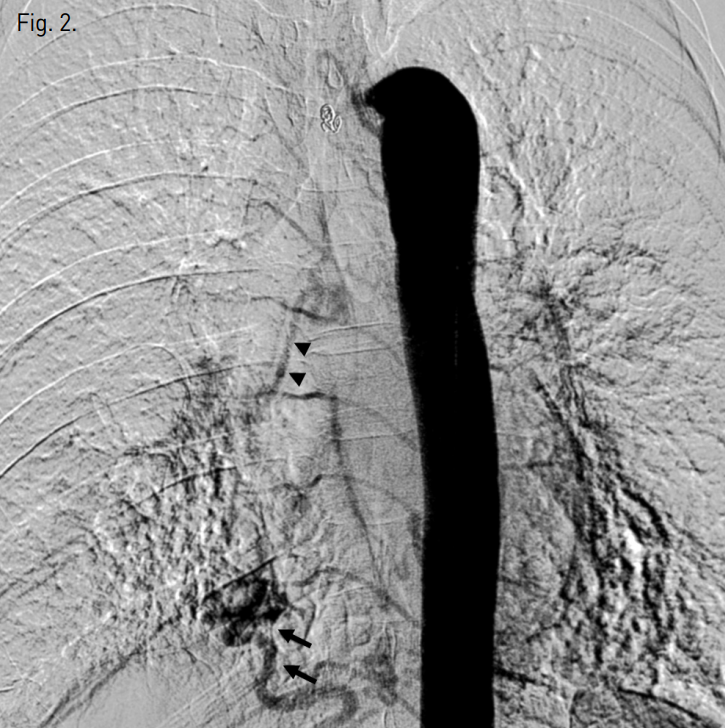

흉부 CT에서 양측 하엽과 우중엽에 기관지 확장증이 있으며 굵어져 있는 기관지동맥 및 우측 아래횡격막동맥이 관찰된다(Fig. 1). 대동맥조영술에서도 기관지동맥 및 우측 아래횡격막동맥이 굵어져있다(Fig. 2).

Fig. 1

Chest CT shows bronchiectasis in right middle lobe and both lower lobes and tortuous engorged inferior phrenic artery (arrows).